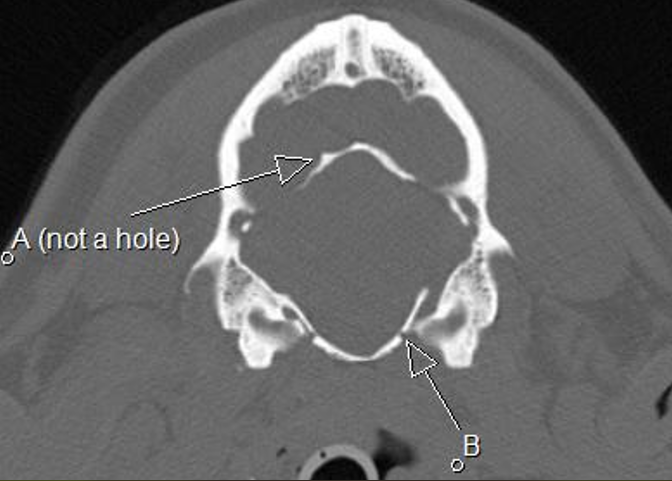

A dorsum sella B oval foramen